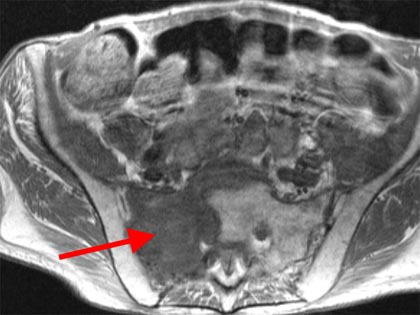

Schmerzsyndrome der Wirbelsäule; Bandscheibenvorfall; Verschleiß der Bandscheiben; Spinalkanalstenose (Verengung des Wirbelkanals); Instabilitäten; Spondylolisthesis (Wirbelgleiten), Myelopathie (Schädigung des Rückenmarkes); Querschnittslähmung; Erkrankungen bei Kinder und Heranwachsenden (z. B. Formveränderungen, Skoliosen, Kyphosen, angeborene Wachstumsstörungen, Verletzungen, Entzündungen, Tumore und Metastasen); Verletzungen des Rückenmarks; Wirbelkörperbrüche; Deformitäten (Formveränderungen, Skoliose, Kyphose); Tumore und Metastasen; Infektionen; Spondylodiszitis (Infektion von Bandscheiben und Wirbelkörper); rheumatische Instabilitäten der Halswirbelsäule sowie zwischen Kopf und Halswirbelsäule; rheumatische Veränderungen der Brust- und Lendenwirbelsäule (z. B. Morbus Bechterew);Verengungen des Foramen magnum; muskulärer Schiefhals; Syndrome durch die erste Rippe; Deformitäten des Thorax (z. B. Trichterbrust, Kielbrust); Erkrankungen und Verletzungen der Rippen; etc.